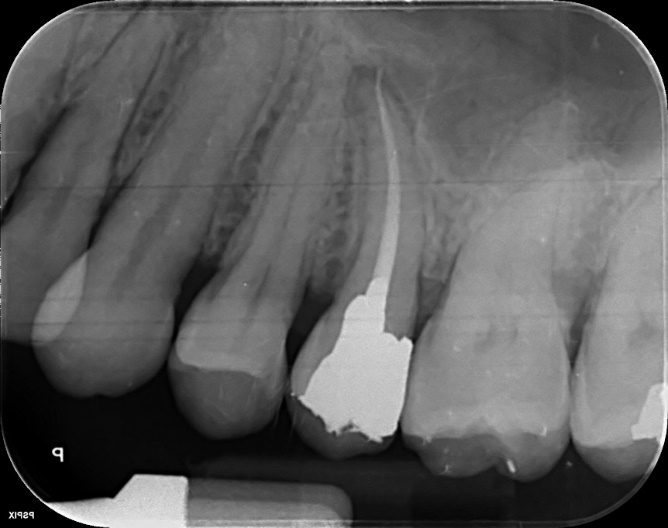

Upper Premolar and Molar root canal treatment and restoration